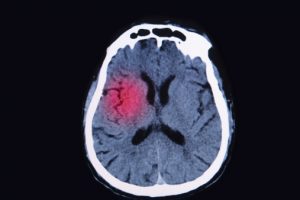

A TBI occurs when there is a blow, bump, or jolt to the head region, disrupting the normal function of the brain. TBIs can range in severity and not all head injuries result in a TBI. A mild version of a TBI is a concussion, which is a common occurrence.

Single traumatic brain injury can initiate Alzheimer’s disease-like neurodegeneration

A single traumatic brain injury can initiate Alzheimer’s disease-like neurodegeneration, according to a Penn State study. The researchers found that years after a TBI, the brain still reveals changes evidencing that Alzheimer-like neurodegeneration may have been initiated or accelerated after a single TBI occurrence.

TBI survivors revealed high density and wide distribution of neurofibrillary tau tangles and amyloid-beta plaque pathology much greater than the age-matched, healthy controls. Furthermore, nearly one-third showed neurodegeneration similar to that in Alzheimer’s disease in those with only one TBI.